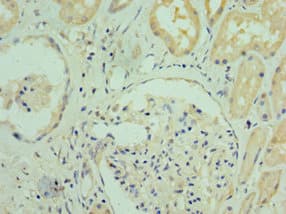

Rabbit Polyclonal RGS20 antibody. Suitable for WB, IHC-P, ICC/IF and reacts with Mouse, Human samples. Immunogen corresponding to Recombinant Fragment Protein within Human Regulator of G-protein signaling 20 aa 1-250.

Applications ICC/IF, IHC-P, WB

Species Reactivity Human, Mouse